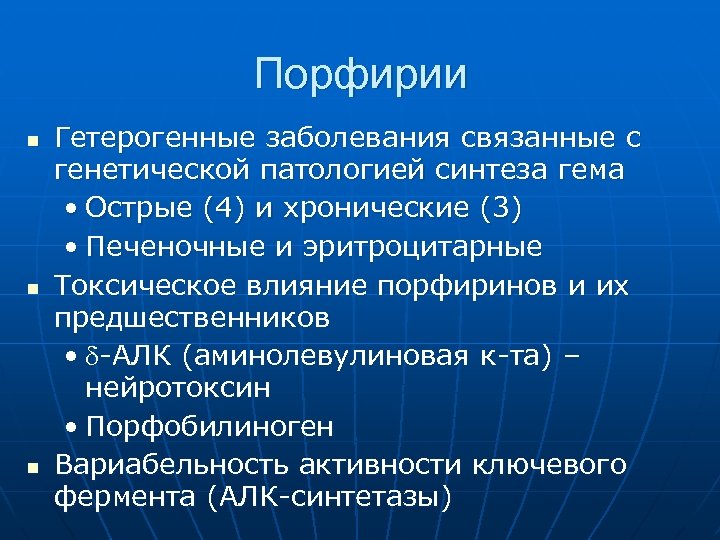

Порфирии n n n Гетерогенные заболевания связанные с генетической патологией синтеза гема • Острые (4) и хронические (3) • Печеночные и эритроцитарные Токсическое влияние порфиринов и их предшественников • -АЛК (аминолевулиновая к-та) – нейротоксин • Порфобилиноген Вариабельность активности ключевого фермента (АЛК-синтетазы)